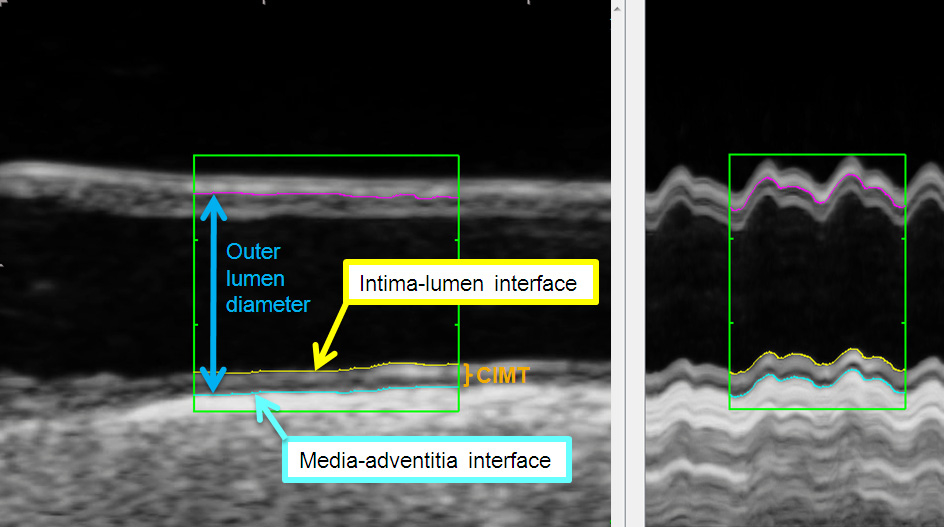

a) CIMT is defined as the viewable distance between the lumen-intima- and the media- adventitia interface (see fig. 1).

Figure 1

Ultrasound image of the common carotid artery (longitudinal axis) with tracing lines of automatic contour-detection at the lumen-intima- (yellow line) and the media- adventitia interface (blue line). Outer lumen diameter (between blue- and pink-coloured line) in the common carotid artery in B-mode (left) over two heart cycles and with M-mode (right) generated by 180 single images of a this clip. The mean CIMT at the far wall was 0.87 mm.

Originally, CIMT-measurements were performed via a manual method that could be integrated in ultrasound systems or per additional acquired software. However, the last few years it could be demonstrated that this method is associated with a higher reader-subjectivity compared to automatic or semiautomatic (automatic + manual correction) measurement software [21]. These can be implemented in the ultrasound system or can base a) on an image-analysis (contour-detection) (fig. 1, [22]) or b) on the analysis of radiofrequency signals. The radiofrequency – analysis is performed with single images or continuously over more heart cycles.